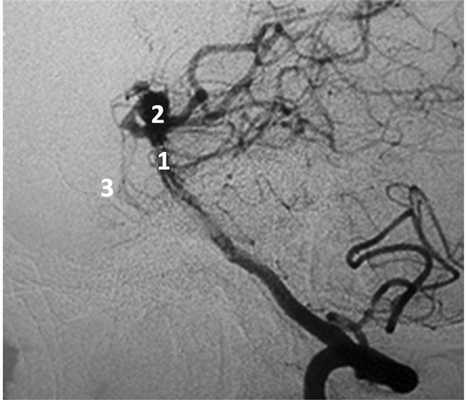

Рис. 3. Левосторонняя вертебральная ангиограмма, боковая проекция с разворотом больной П., 50 лет: АА бифуркации БА. 1 — базилярная артерия, 2 — аневризма бифуркации базилярной артерии, 3 — спинка турецкого седла.

Рис. 4. Клипирование аневризмы бифуркации базилярной артерии больной П., 50 лет. а — правосторонняя птериональная краниотомия, доступ через ретрокаротидный промежуток (вид через микроскоп); б — вид через эндоскоп с тубусом 30° через ретрокаротидный промежуток. 1 — базилярная артерия, 2 — задняя мозговая артерия, 3 — шейка аневризмы (обозначена пунктиром), 4 — шпатель на базальной поверхности лобной доли мозга, 5 — шпатель на медиальной поверхности височной доли мозга, 6 — контралатеральная задняя мозговая артерия, 7 — контралатеральный глазодвигательный нерв.